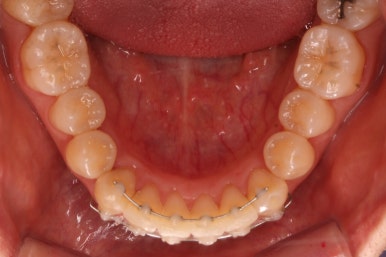

마찬가지로 부산설측교정 키다리아저씨치과에서 처음 내원하셨을 당시의 입안 모습입니다.

어금니쪽은 특별히 이상이 없었고, 위아래 앞니만 삐뚤한 상태였습니다.

부산설측교정 키다리아저씨치과에서 장치를 부착한 이후의 모습입니다.

환자분은 교정장치가 보이는 것을 좋아하지 않으셔서 윗니는 부산설측교정 하는 콤비교정으로 진행했습니다.

콤비교정이란 윗니는 설측교정(안쪽으로 하는 교정), 아랫니는 바깥으로 하는 일반 교정을 조합해서(콤비)하는 교정치료를 뜻합니다.

사용한 장치는 부분교정에 특화 되어있는 부피가 작고 눈에 잘 띄지 않는 MTA라는 장치를 이용하였습니다.